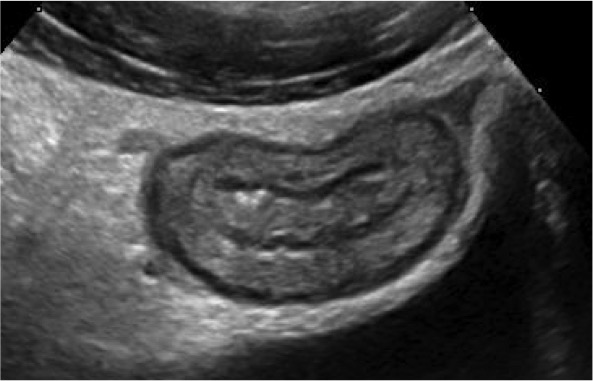

The study currently has 66 children with IBD and 66 healthy comparison participants. Each of the 66 IBD patients and 66 comparison participants have had fasting plasma glucose, lipid profile, high sensitivity C-reactive protein, carotid-femoral pulse wave velocity (PWV), carotid intima-media thickness (cIMT), abdominal aorta intima-media thickness (aIMT), and retinal vascular calibre performed. Recruitment is nearing completion and analysis of the above measures has commenced.

Image: Assessment of the carotid artery by ultrasound